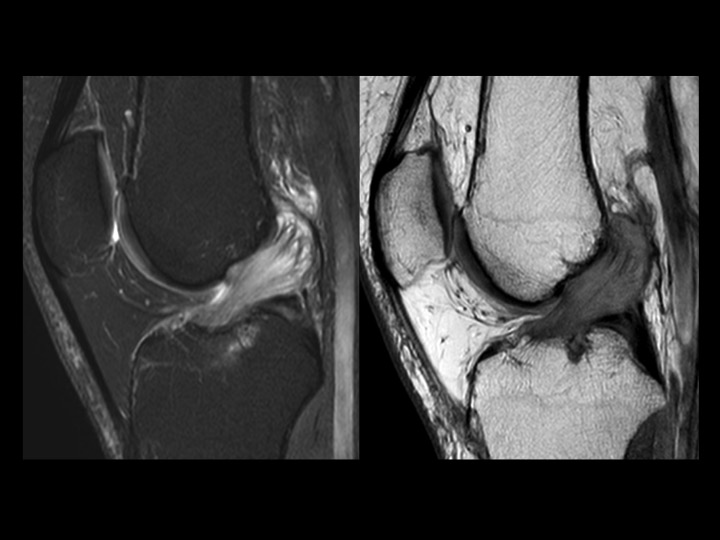

44M worsening knee pain

There is diffuse intrasubstance mucoid degeneration and expansion of the ACL with only small septated ACl ganglion near the femoral origin. This is typically seen in older individuals, but I like to think this gentleman is quite young. No other pathology on MRI. Apparently treatment is varied; Ive only found small series with good outcomes, but no mention of time to clinical follow up. It seems in this case that judicious debridement would be difficult, as the entire ligament seems to be rotten to the core. Reference article.

anterior cruciate ligament ( RID2781 )